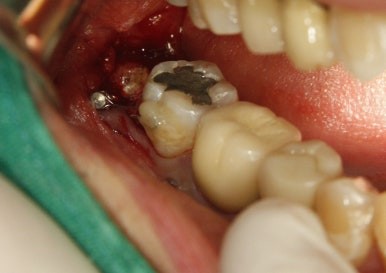

수술날짜를 잡고 나머지 뿌리도 깨끗하게 발치완료~